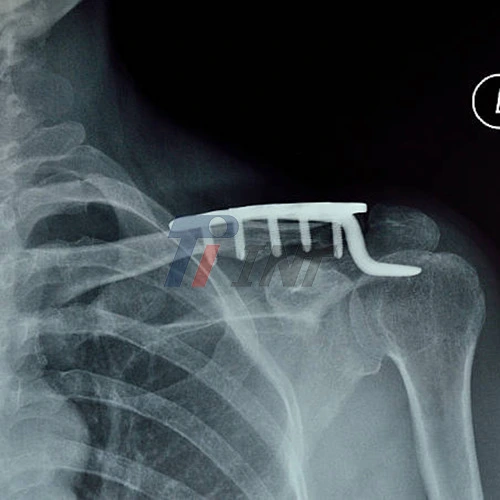

The advent of titanium plate for collar bone treatment heralded a new era in orthopedic care. Titanium's unique properties, including its biocompatibility and high strength-to-weight ratio, made it an ideal material for medical implants. The development of advanced titanium alloys, such as Ti6Al4V ELI (Extra Low Interstitial), further enhanced the performance of these plates.

The field of orthopedic implant design has witnessed remarkable technological advancements, particularly in the development of titanium plates for collar bone treatment. These innovations have focused on enhancing the efficacy, safety, and patient comfort associated with collar bone surgeries.

One of the most significant advancements is the implementation of computer-aided design (CAD) and 3D printing technologies in the production of titanium plates. This approach allows for the creation of patient-specific implants that perfectly match the anatomy of the individual's collar bone. Custom-designed plates ensure optimal fit and stability, reducing the risk of complications and improving overall surgical outcomes.

Another noteworthy development is the introduction of low-profile titanium plate for collar bone. These ultra-thin plates minimize soft tissue irritation and reduce the likelihood of implant prominence under the skin. The low-profile design is particularly beneficial for patients with less subcutaneous tissue, as it helps prevent discomfort and potential complications associated with implant palpability.